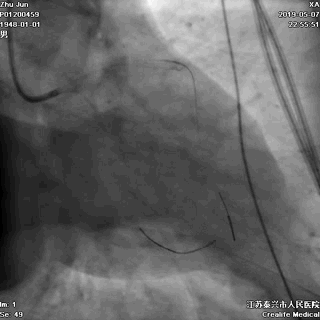

三、球囊扩张病变

---打通生命通道

前降支至左主干行PTCA

四、STENT植入

---巩固胜利成果

前降支植入第一枚STENT

前降支-左主干STENT定位和植入